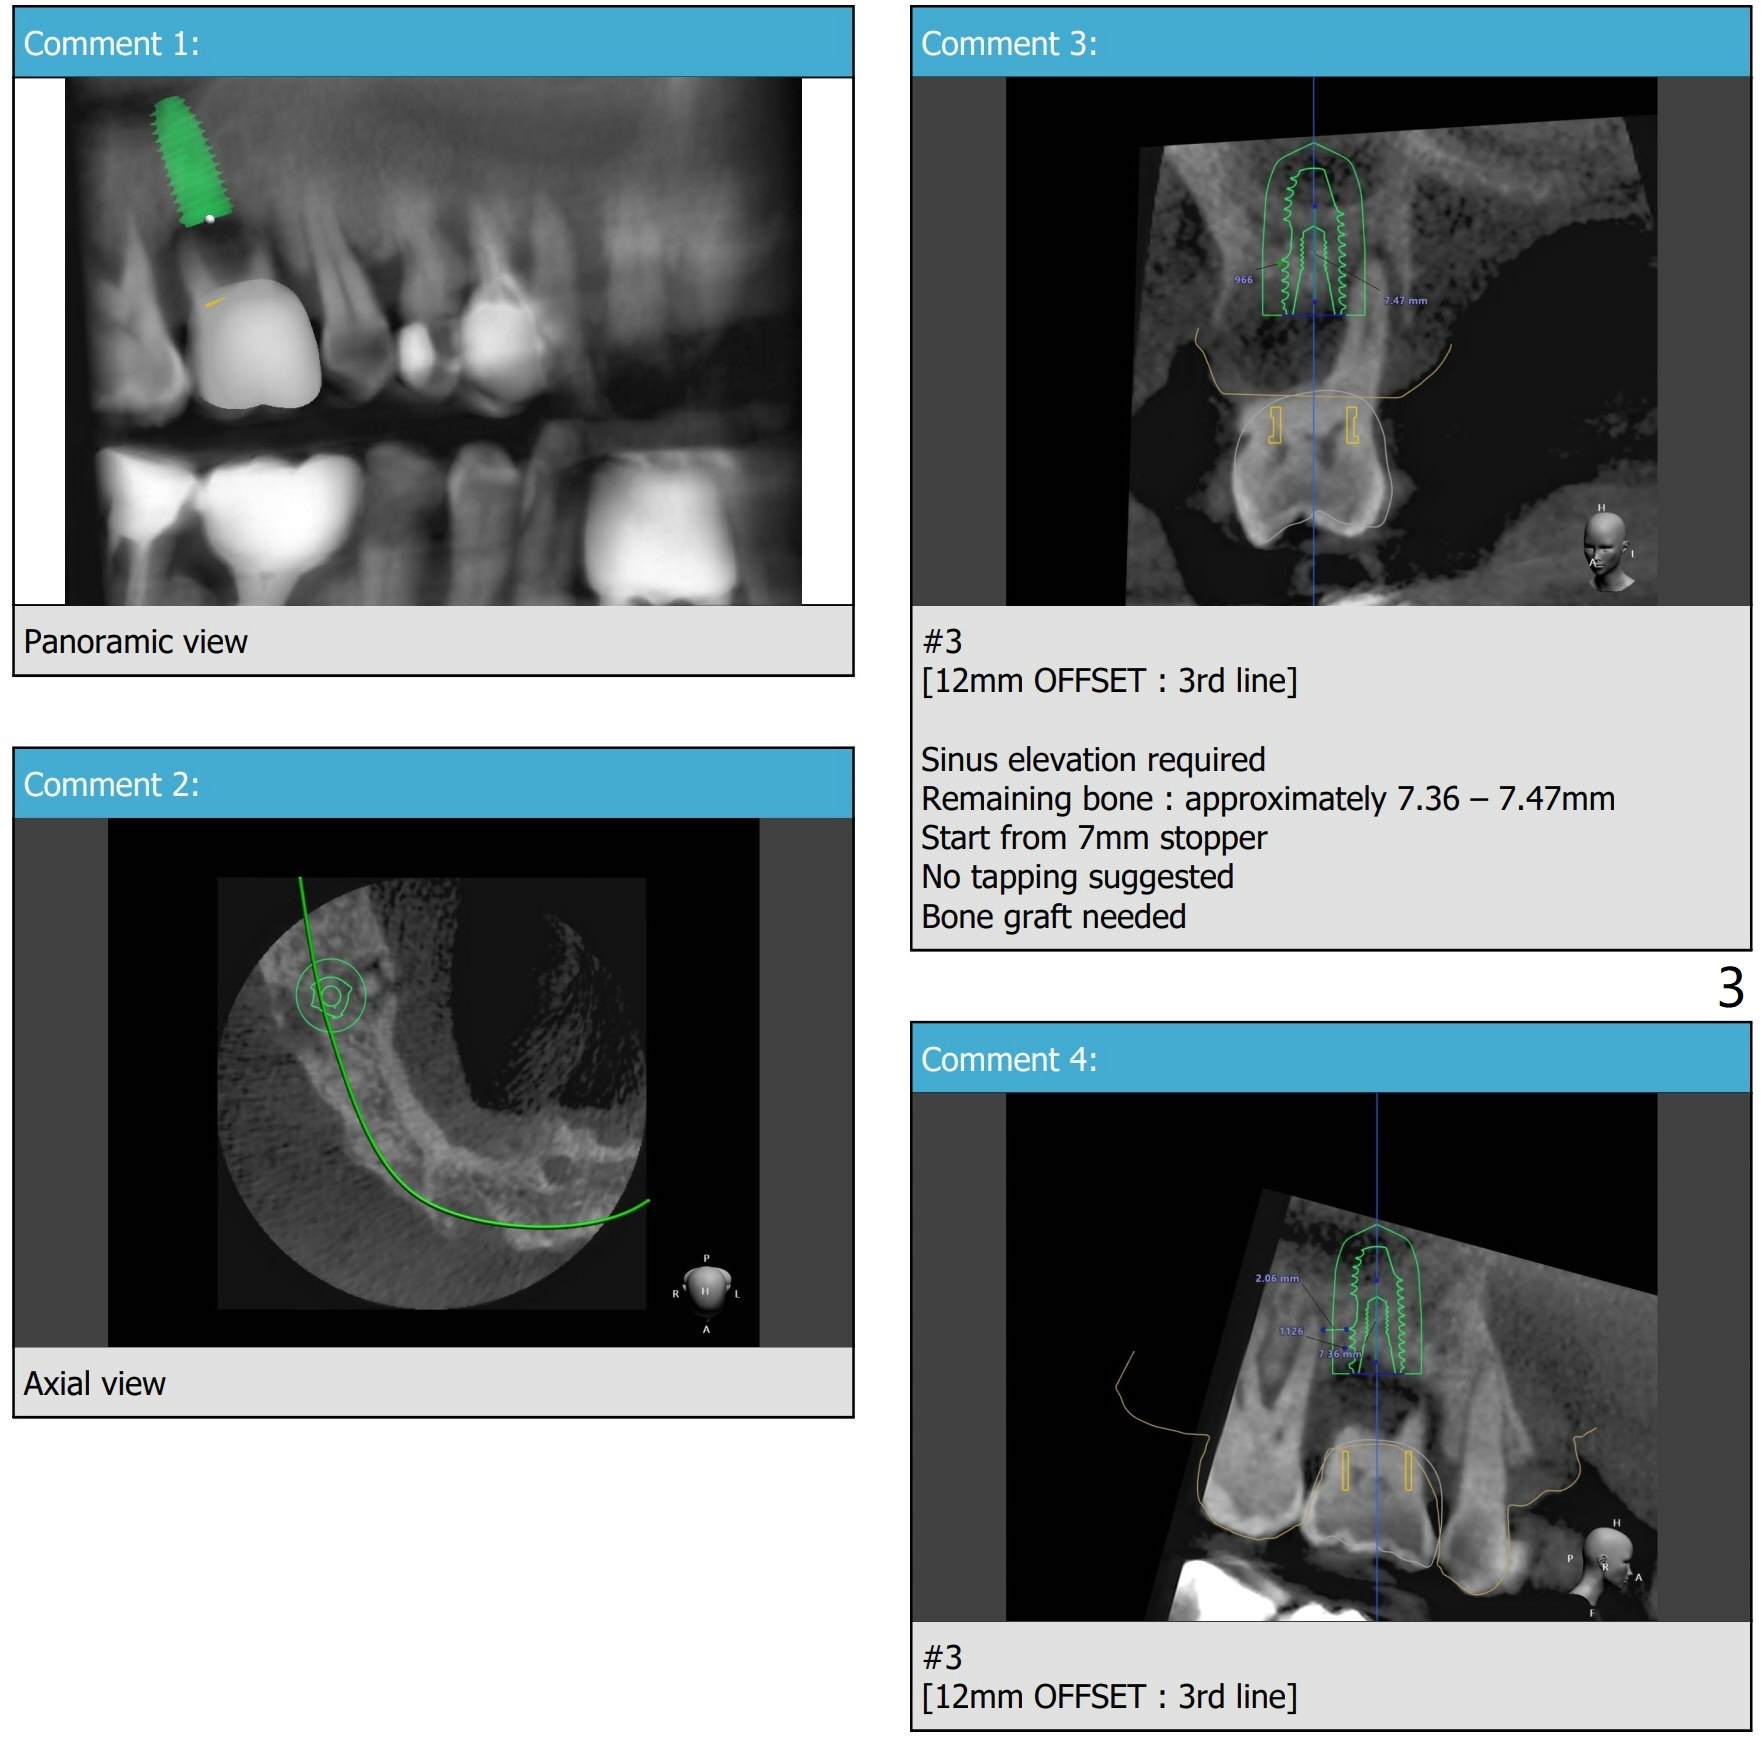

Implant Placement Level and Angulation to Sinus Floor

Return to No Deviation Torque 劈开术